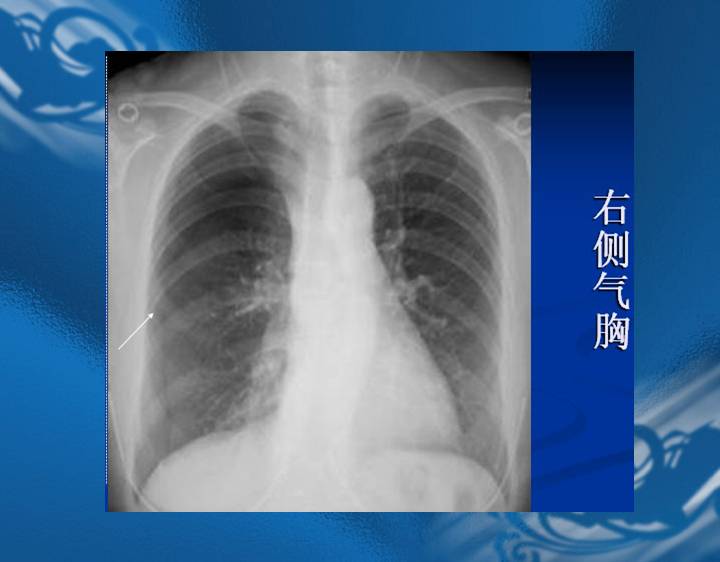

执业医师资格考试“实践技能”影像学辅导资料